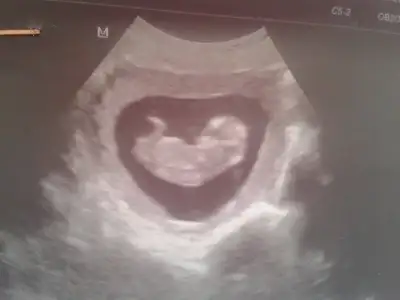

Hastaneden geldim son halimiz 18 haftalikmis bi bakın kizlarrrrr belki gorursunuz

Genel olarak erkek diye tahminler yapildi ama kizmis bebegim.fikir olur size diye tekrar yukluyorun resmini